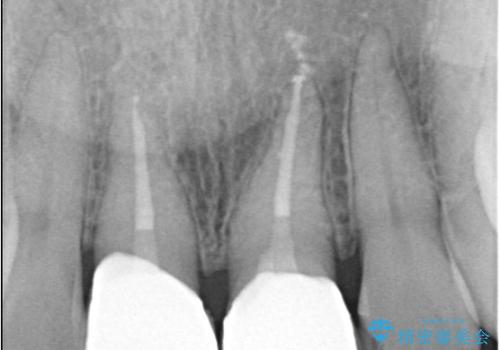

- 気を失って転倒し、前歯をぶつけたことをきっかけに「かかりつけ医で抜歯と診断された」との主訴で来院された患者様です。

レントゲン撮影や顕微鏡下での精査、メチレンブルーによる染色検査を行った結果、破折線は認められず、保存可能と判断しました。

精密根管治療を行い、その後オールセラミッククラウンで審美的に修復しています。あわせてホワイトニングとエアフローによるクリーニングも行い、自然で美しい仕上がりとなりました。